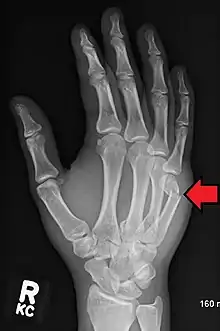

| Boxer's fracture of the 5th metacarpal head from punching a wall | |

A boxer's fracture is the break of the 5th metacarpal bones of the hand near the knuckle.[4] Occasionally it is used to refer to fractures of the 4th metacarpal as well.[1] Symptoms include pain and a depressed knuckle.[2]

Classically, it occurs after a person hits an object with a closed fist.[3] The knuckle is then bent towards the palm of the hand.[3] Diagnosis is generally suspected based on symptoms and confirmed with X-rays.[3]

Diagnosis by a doctor's examination is the most common, often confirmed by x-rays. X-ray is used to display the fracture and the angulations of the fracture. A CT scan may be done in very rare cases to provide a more detailed picture.